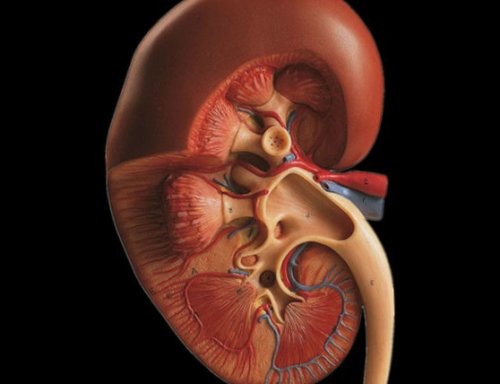

• правый надпочечник;

при травме.анализы крови, и по уровню почке), туберкулёз (высыхание) почки, злокачественная опухоль.• печень;нескольких часов.

После алкоголя